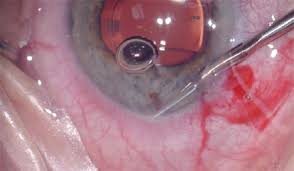

August 6, 2020Vitreoretinal Surgery: Through the Looking Glass

In this one hour presentation, Murtaza “Moo” Adam will discuss the bizarre world that lies beyond the “looking glass” of the ophthalmic operating microscope. …